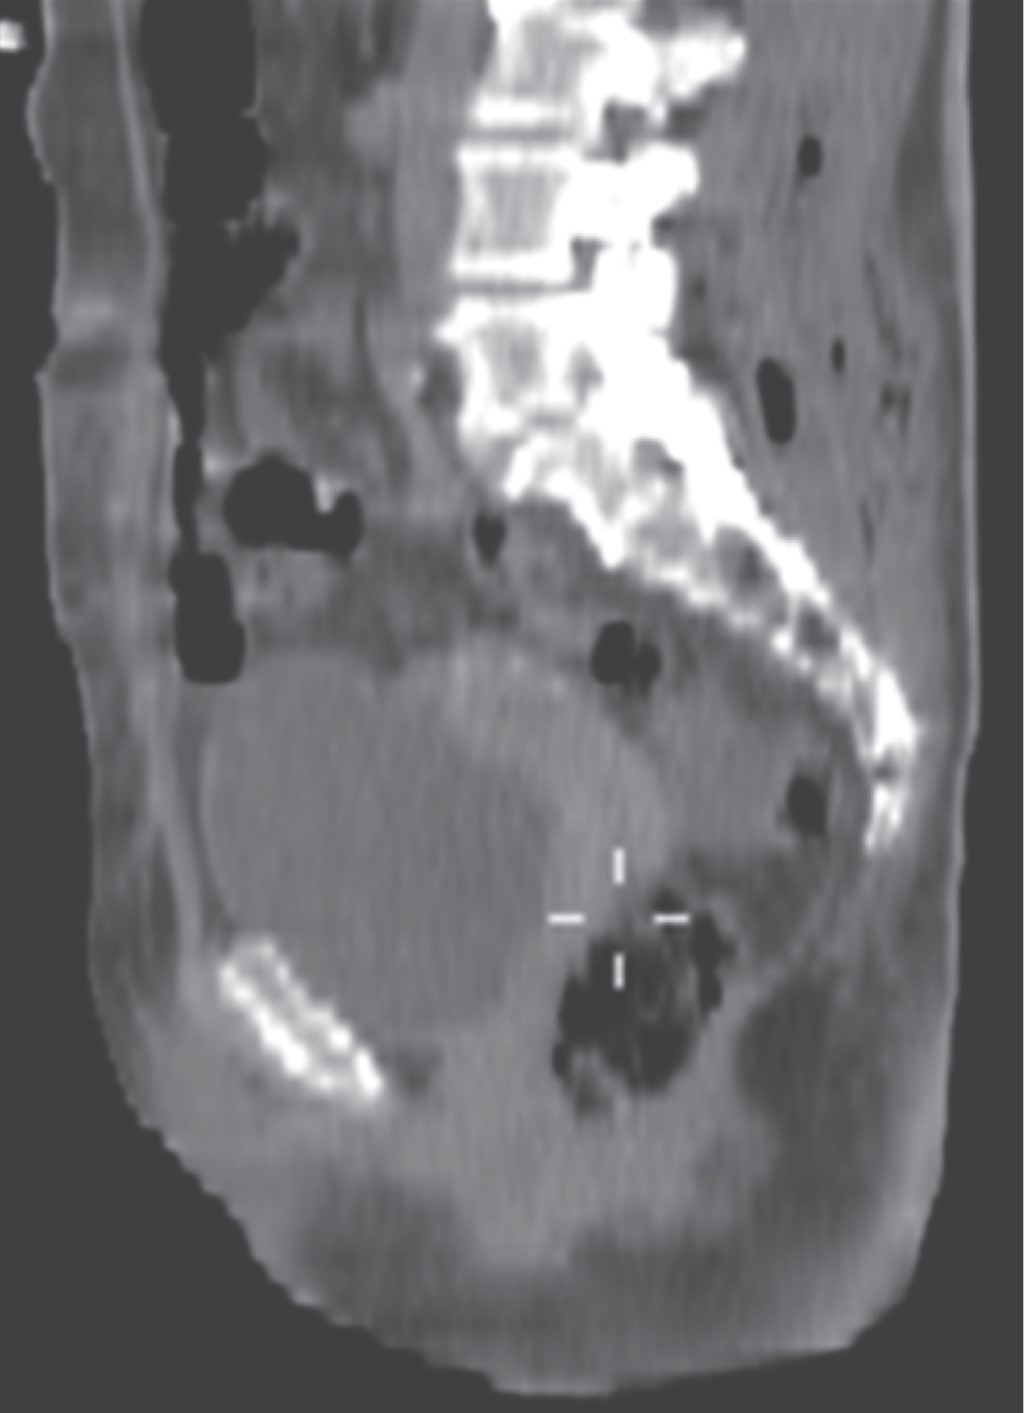

Necrotizing fasciitis due to Klebsiella pneumoniae secondary to intramuscular gluteal injection managed with a negative pressure system

Necrotizing fasciitis is a serious, rare and fast progressing infection, which that is difficult to diagnose in the early stages. It produces thrombosis of the microcirculation with involvement of the subcutaneous cellular tissue and muscle fascia and is related to high mortality. Documented cases of necrotizing fasciitis in which Klebsiella pneumoniae is the etiologic agent are extremely rare and have a mortality rate of 70%. We present the case of a 57-year-old woman who developed necrotizing fasciitis after an intramuscular injection in the right gluteus. She was handled with negative pressure therapy at the General Hospital of Zacatecas "Luz González Cosío" showing a good progress, with satisfactory functional and aesthetic results. The negative pressure therapy facilitated the treatment and evolution of the patient considerably, favoring the granulation of the wound and the definitive closure. We underline highlight the usefulness of negative pressure therapy in the management and healing of wounds, staving off avoiding complex reconstructive surgeries.

Figure 2